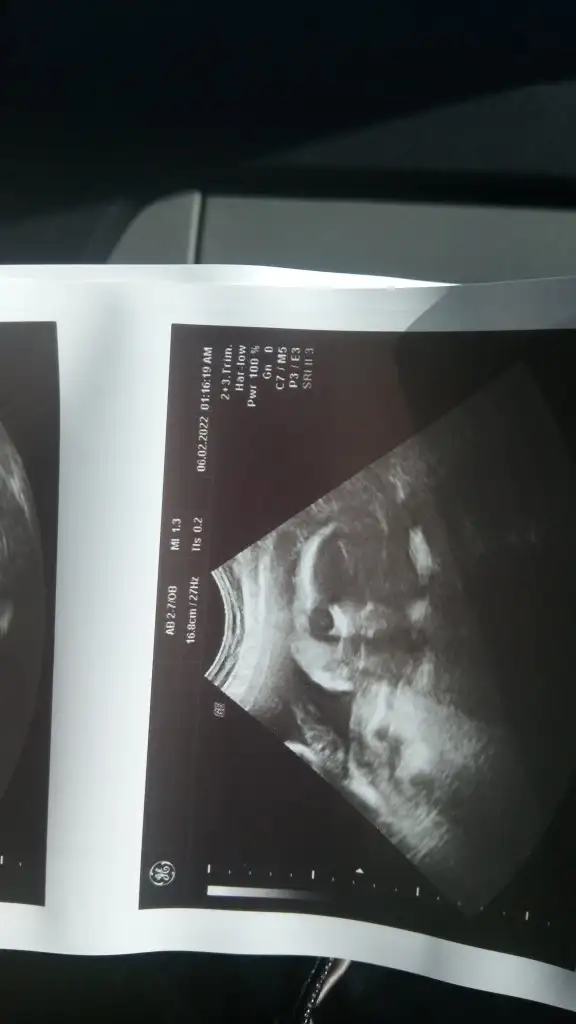

sakinsampiyonn Azize hanımın boşluğu varmış, randevu aldım ama siyah beyaz veriyorlar görüntü dedi. Çok anlayamadım. Senin paylaştıkların siyah beyaz diye mi geçiyor acaba

Yok Etimesgut canım. Yeni gelmiş herhalde. Çok tatlı bir kadındı baya baktı. Yan duruyor dedi sadece eşim görebildi. Cihazı eskiydi biraz o yüzden sendeki gibi görüntü alamadık. Bu var sadeceAlife etimesgut canim sen pursaklarami gittin acaba Azize hanim yok cunku hastanede